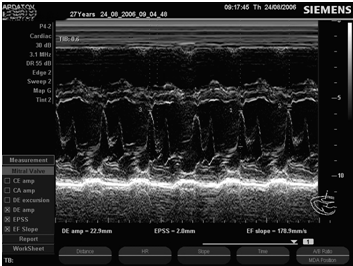

ЭхоКГ-критерии ПМК в М-режиме

1.       Позднесистолическое или голосистолическое выгибание одной или обеих створок по направлению к задней стенке левого предсердия более 3 мм.

2.       Диастолическое трепетание створок митрального клапана.

.        Увеличение диастолической экскурсии передней митральной створки.

.        Увеличение скорости раннего диастолического прикрытия передней митральной створки.

.        Увеличение систолической экскурсии межжелудочковой перегородки.

.        Увеличение систолической экскурсии задней стенки левого желудочка.

.        Дилатация аорты и увеличение ее систолической экскурсии.

Рис. 7. ПМК, М- и В-режим, длинная ось левого желудочка, парастернальный доступ.